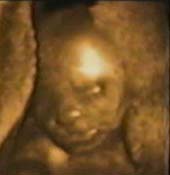

William3.jpg, 17/11/2003, 16 kB